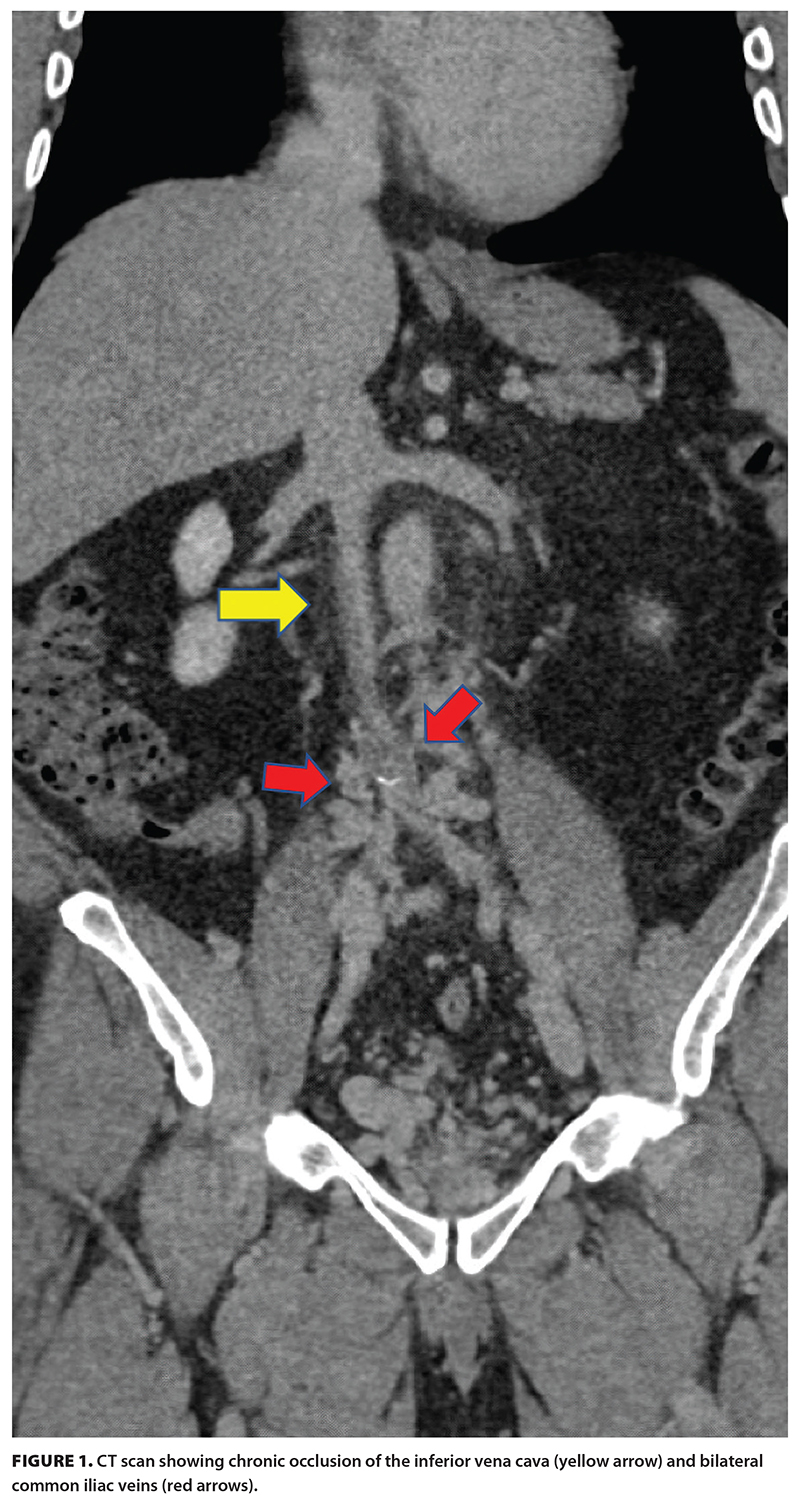

In December 2024, the patient was brought to the angiography suite at Vancouver General Hospital and placed under general anesthesia. Under fluoroscopy, catheter-directed venography showed chronic right lower extremity deep vein thrombosis and iliocaval occlusion with extensive venous collaterals [Figure 2]. Mechanical thrombectomy of the right iliofemoral deep vein thrombosis was performed with subsequent recanalization of the occluded iliocaval veins and venous reconstruction with stents extending from the infrarenal inferior vena cava into the bilateral external iliac veins. On day 1 postprocedure, check venography was performed with augmentation of the stent constructs through balloon dilation, which resulted in widely patent stents and antegrade flow with no residual filling of the collaterals. The patient was discharged 1 day later with daily low-dose aspirin and therapeutically dosed low-molecular-weight heparin.

The patient lost 13 kg in 3 weeks due to improvement of their venous hypertension and resultant reduction in edema. They were able to advance from walking with a cane to hiking and biking without assistance. They returned to a fit and active lifestyle, nearing their prelymphoma diagnosis status, with a Villalta score of 1. Follow-up assessment 1 year postintervention demonstrated ongoing patency of the stents [Figure 3]. The patient is managed by our multidisciplinary hematology and interventional radiology team and continues to do very well, with no lifestyle limitations.